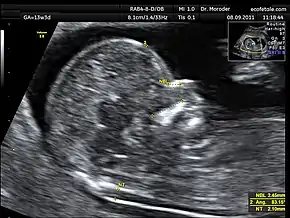

Measurements of fetal nuchal translucency, nasal bone and facial angle according to the standards of the Fetal Medicine Foundation

Procedure

Nuchal scan (NT procedure) is performed between 11 and 14 weeks of gestation, because the accuracy is best in this period. The scan is obtained with the fetus in sagittal section and a neutral position of the fetal head (neither hyperflexed nor extended, either of which can influence the nuchal translucency thickness). The fetal image is enlarged to fill 75% of the screen, and the maximum thickness is measured, from leading edge to leading edge. It is important to distinguish the nuchal lucency from the underlying amniotic membrane.[8]

How to define a normal or abnormal nuchal translucency measurement can be difficult. The use of a single millimeter cutoff (such as 2.5 or 3.0 mm) is inappropriate because nuchal translucency measurements normally increases with gestational age (by approximately 15% to 20% per gestational week from 10 to 13 weeks).[9] At 12 weeks of gestational age, an "average" nuchal thickness of 2.18mm has been observed; however, up to 13% of chromosomally normal fetuses present with a nuchal translucency of greater than 2.5mm. Thus for even greater accuracy of predicting risks, the outcome of the nuchal scan may be combined with the results of simultaneous maternal blood tests. In pregnancies affected by Down syndrome there is a tendency for the levels of human chorionic gonadotropin (hCG) to be increased and pregnancy-associated plasma protein A (PAPP-A) to be decreased.